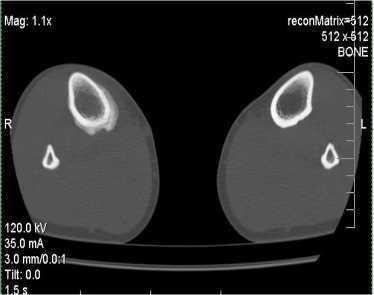

Нами с помощью рентгенографии прослежена картина ПН у 12 пациентов (9 мужчин и 3 женщины в возрасте 14-40 лет): в области плюсневых костей стопы (у 6) (рисунок 1) и одного в пяточной кости (рисунок 2), в проксимальном метафизе большеберцовой кости (у 3) и у двоих - в дистальном и проксимальном метафизе бедра (рисунок 3-5). При этом у одного пациента - перелом напряжения проксимальных отделов бедренных костей с двух сторон. Большинство пациентов предъявляли жалобы на боли в стопе или голени, возникшие после продолжительных физических нагрузок (спортивный бег, однообразная физическая работа). Боль прекращалась в покое. При осмотре наиболее болезненная точка, как правило, совпадала с локализацией зоны перестройки в костном аппарате. Болевые ощущения у большинства пациентов носили центральный характер и не были похожи на боли при бурсите или тендовагините. Вместе с тем, у некоторых из них, не связанных со спортом, анамнестические данные о нагрузках носили неопределенный

Из перечня других методик исследования компьютерная томография (КТ) не обладает решающим значением в диагностике обычных ПН. Однако, в выявлении продольных ПН, по сравнению с общепринятой рентгенографией, КТ отличается большим разрешением. Кроме того, КТ считается ведущим методом в определении различий между опухолевой массой и избыточной костной мозолью. Наибольшие трудности могут возникать при большой толщине томографических срезов, в связи с чем рекомендуется производить срезы толщиной в 1-2 мм на аппаратах высокого разрешения.